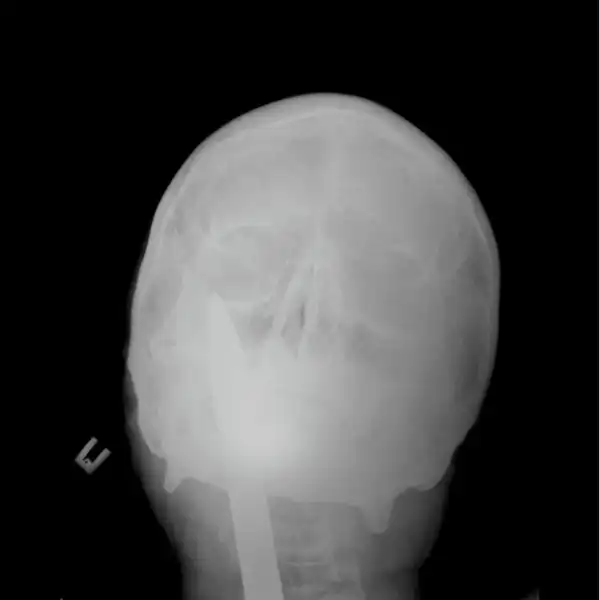

Мужчина упал на лом не повредив жизненно важных органов, говорят после операции выписан в удовлетворительном состоянии домой.

Счастливчик 80 уровня, на снимках и правда видно ни мозг, ни глотку не повредил, везунчик.

Тоже долго башку ломал, пока не дошло - на второй фотке они уже извлеченный лом сверху на простыню положили